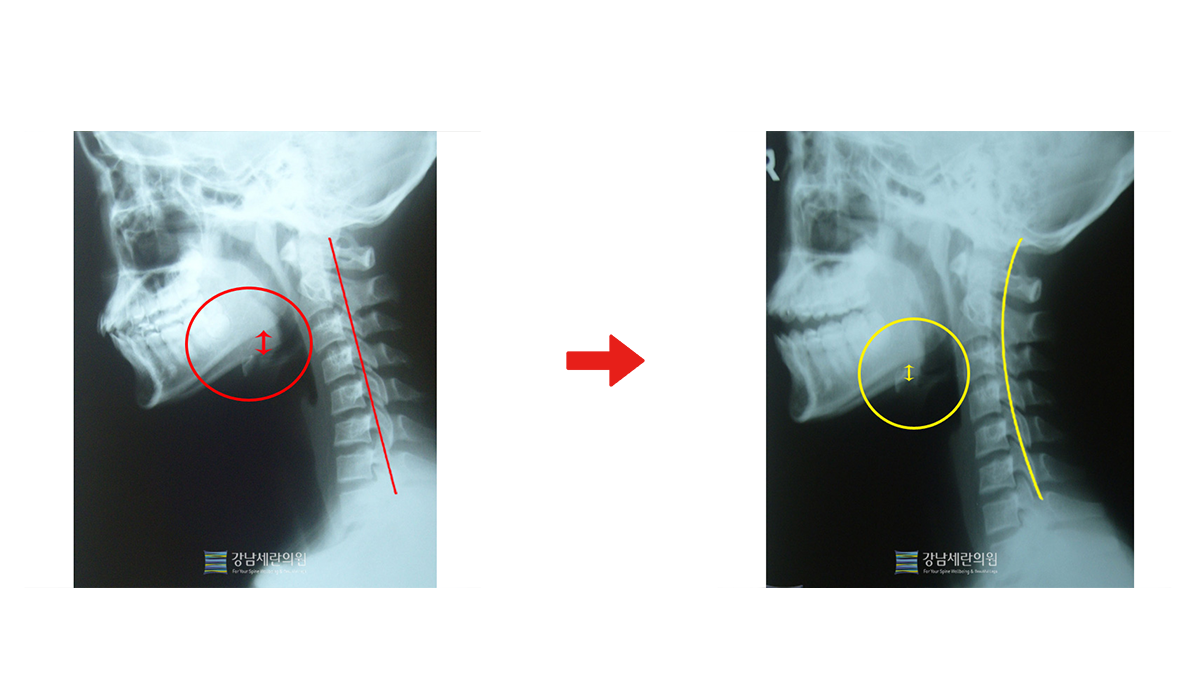

#일자목

일자목 치료 전 ▶ 일자목 30회(3개월) 치료 후